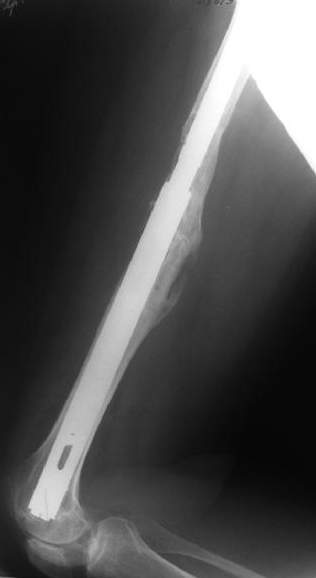

Female, rheumatoid, THA in 2003, car accident in 2006, failed plating. Nailing in Oct 2007. The nail is solid with hollow proximal part where the stem is docked. Last images are in 1 year after

nailing.